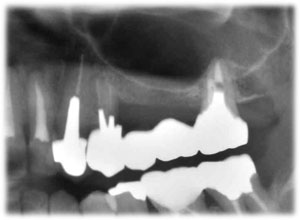

| 術前 | ソケットリフト手術 | 術後2年歯根周囲骨造成良好 |